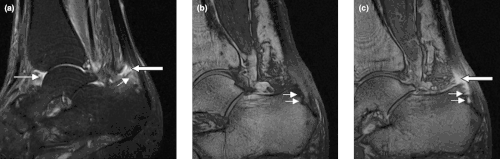

Sagittal magnetic resonance images of ankle region: psoriatic arthritis. (a) Short tau inversion recovery (STIR) image, showing high signal intensity at the Achilles tendon insertion (enthesitis, thick arrow) and in the synovium of the ankle joint (synovitis, long thin arrow). Bone marrow oedema is seen at the tendon insertion (short thin arrow). (b, c) T1 weighted images of a different section of the same patient, before (panel b) and after (panel c) intravenous contrast injection, confirm inflammation (large arrow) at the enthesis and reveal bone erosion at tendon insertion (short thin arrows).